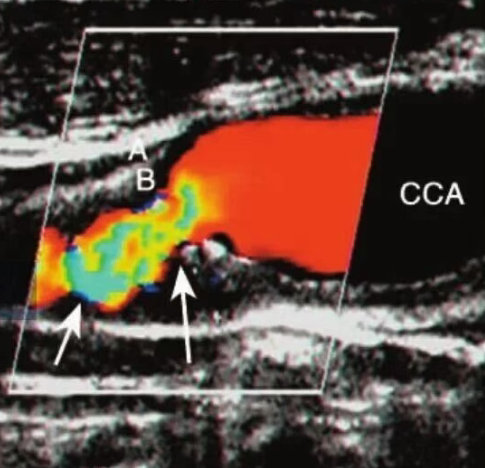

如果斑块的表面不光滑、不规则,同时回声比较弱,这种斑块一般富含更多脂质,被称之为软斑块,相对来说更容易逆转。

需要注意的是,软斑块也更容易脱落,引发脑中风的概率也更高一些,需要我们高度重视,及时进行干预、治疗。